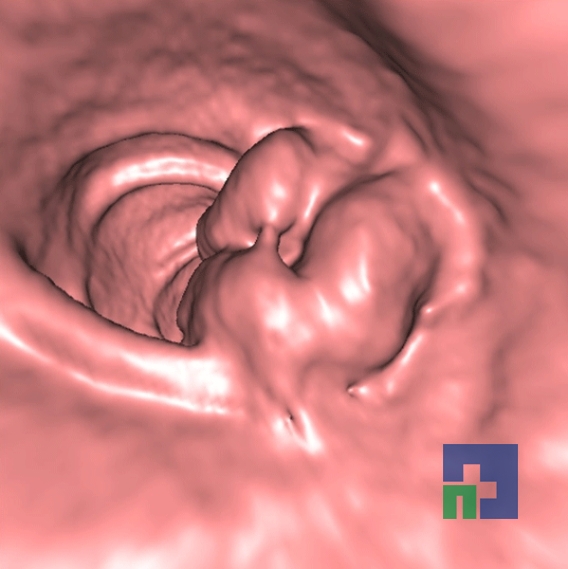

- Empiemul subdural

- Abcesul cerebral

- Fistula carotido-cavernoasa

- Higroma